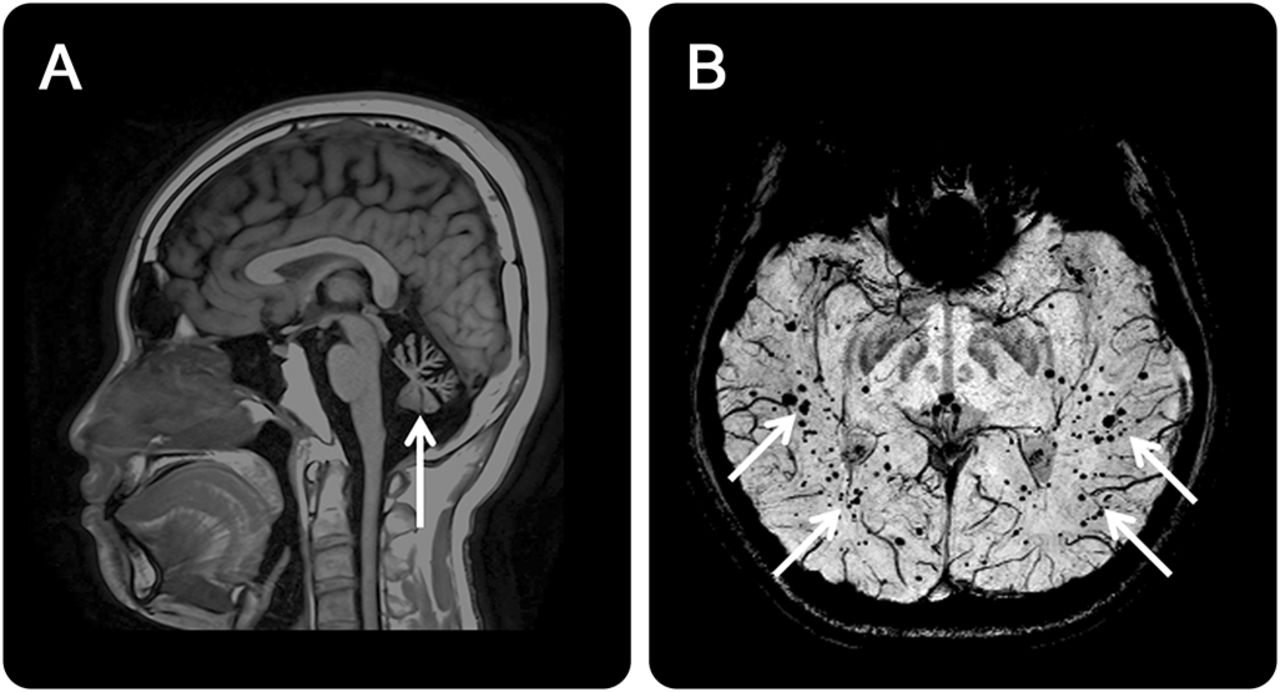

(一)t1加权磁共振成像显示小脑萎缩(箭头所指)。(B) Susceptibility-weighted图像(瑞士)显示点状的信号空间散射在正常大脑(箭头),表明microbleeds含铁血黄素沉积,有相关的扩张血管ataxia-telangiectasia患者中。